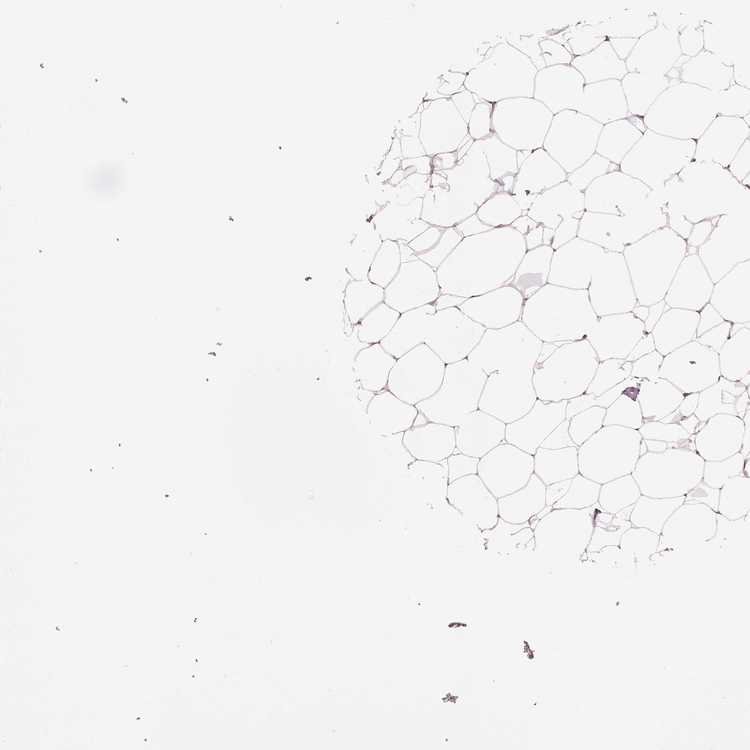

BREAST - Antibody stainingi

Antibody staining in the annotated cell types in the current human tissue is reported as not detected, low, medium, or high, based on conventional immunohistochemistry profiling in selected tissues. This score is based on the combination of the staining intensity and fraction of stained cells.

Each image is clickable and will lead to virtual microscopy that enables deeper exploration of all samples and also displays staining intensity scores, fraction scores and subcellular localization as well as patient and tissue information for each sample.

Antibody HPA069797

Adipocytes Low

Glandular cells Not detected

Myoepithelial cells Not detected